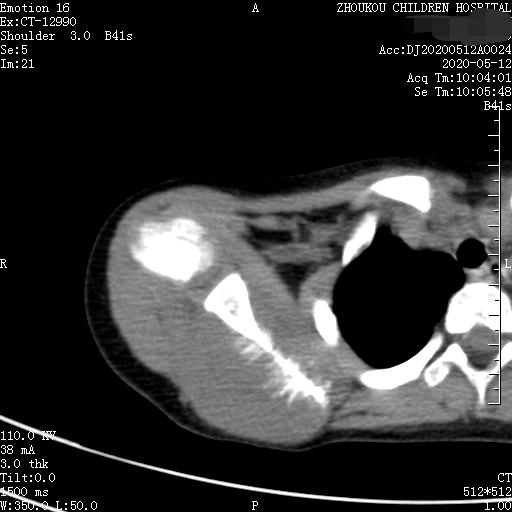

三、常需要鉴别的诊断是骨转移瘤,年龄比较大再就是慢性化脓性骨髓炎病程比较长,好发于长骨骨干。

转移性骨肿瘤是最常见的恶性骨肿瘤,约占恶性骨肿瘤的75%。CT表现一般为溶骨型、成骨型、混合型。同一肿瘤的转移可表现为溶骨与成骨转移两种类型,同一病灶上可出现溶骨与成骨两种表现,少数转移灶呈囊状膨胀性破坏。脊柱的溶骨性转移累及附件并形成椎旁软组织肿块。前列腺癌、结肠癌、类癌的成骨性肋骨转移可表现为膨胀性硬化。前列腺癌容易转移到骨盆,鼻咽癌容易转移到脊柱。肾癌骨转移常为单发、溶骨性且呈多囊状或泡沫状,可伴有骨性房隔、局部膨胀性改变。颅骨溶骨性转移灶有时在溶骨区中央可见残留的正常骨或者密度增高骨,即常说的靶性病变。 术后随访家属得知:病人术后临床医生怀疑骨转移瘤(孩子过去有视网膜母细胞瘤一侧眼球摘除史)或神经外胚层性肿瘤?,建议基因方面检测。